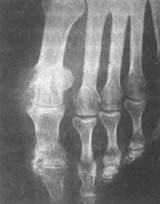

5.X線檢查之表現可助診斷:早期關節囊腫脹,爾後出現骨端出現圓形或半圓形邊緣銳利的穿鑿樣缺損。晚期關節間隙變窄,關節邊緣骨質增生,關節強直,可伴有脫位和病理性骨折。

痛風性關節炎腳趾及趾關節是痛風性關節炎最好發的部位,其中又以腳拇趾關節最為常見,其次為跗、踝、跟、手指關節,再次為掌指關節及腕、肘、膝關節等。較大的關節如髖、肩、骶髂、關節受累機會較少。而下頜、胸鎖、脊柱、胸肋等關節發生痛風性關節炎則更為少見。痛風性關節炎主要侵犯手、腳、踝、腕等人體末端的小關節,而軀幹部位的關節較少發生痛風性關節炎。這是因為這些末端的小關節具有以下幾個有利於血尿酸沉積的特點:

痛風性關節炎典型的首次發作的痛風性關節炎多為單關節炎,以第一跖趾及拇趾關節為多見,其次為踝、膝、肘、腕、手及足部其他關節。急性期多起急驟,常在夜間突發,可因疼痛而醒並且徹夜不能入睡。病情反覆發作,則可發展為多關節炎,或遊走性關節炎。受累關節紅、腫、熱、痛,活動受限,大關節受累時常有滲液。可伴有發熱、寒戰、疲倦、厭食、頭痛等症狀。一般歷時1-2周症狀緩解。局部皮膚紅腫轉為棕紅色而逐漸恢復正常。有時可出現脫屑和瘙癢。慢性期尿酸鈉在關節內沉著逐漸增多,發作逐漸頻繁,間歇期縮短,受累關節增多,疼痛加劇,炎症不能完全消退,出現痛風石,痛風石以關節和腎臟較多見,外耳的耳輪、跖趾、指間和掌指關節等處也會出現痛風石,隨著風石的不斷沉積增多,導致關節肥大、畸形、僵硬、活動受限。

(四)慢性關節炎期由急性發病至轉為慢性關節炎期平均11年左右,關節出現僵硬畸形、運動受限。30%左右病人可見痛風石和發生腎臟合併症以及輸尿管結石等。晚期有高血壓、腎腦動脈硬化、心臟梗塞。少數病人死於腎功能衰竭和心血管意外。繼發性痛風病程相似,繼發於血液病、糖原儲存病的間歇期較短。血尿酸檢查增高,最高達20mg%(正常:男7mg%,女6mg%)。偏光顯微鏡發現關節滑液中吞噬了尿酸鹽結晶的白血球。急性期時白血球增高,血沉加快。X線檢查顯示關節軟骨下骨的穿鑿樣破壞以及局部的骨質疏鬆、腐蝕或皮質斷裂,關節間隙狹窄和邊緣性骨質增生。痛風結石可為鈣化陰影。